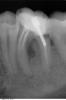

super Опубликовано 4 октября, 2011 Поделиться Опубликовано 4 октября, 2011 Здравствуйте, форумчане. 2 года решил назад поставить брекет-систему на зубы. По рекомендации ортодонта удалил восьмерку снизу слева. Удаление было довольно сложным, зуб лежал в кости, его выдалбливали молотком, резали десну. Хирург сделал настолько большую дырку/разрез в десне, что она не затянулась, до сих пор!Под впечатлениями от этого удаления, не посещал стоматолога 2 года, и вот решился. Опять хочу поставить брекеты, но непонятно, что делать с дыркой в десне, в которой постоянно застревает пища со всеми вытекающими. Проконсультировался в двух стоматологиях. Предлагают следующие варианты (зубы снизу слева): 1) Шестерка не жилец – под удаление Семерка под большим вопросом – возможно так же придется удалить, либо сохранить на время ортодонтического лечения, но потом под снос. Ортодонтическое лечение. В этом случае терапевт говорит, что дырка в десне – это, на самом деле, кариес на седьмом зубе, а десна уже давно заросла. На мой взгляд звучит странно, но я не специалист. 2) Терапевтического лечения пока не требуется. Собственно, ортодонтическое лечение. В будущем, возможно, придется удалить шестерку, но это после брекет-системы. В этом случае терапевт говорит, что десна не затянулась до конца. Но при этом доктор не может найти, как это исправить. Единственное, что было предложено – это делать полоскание ирригатором, исключая тем самым воспалительный процесс. По идее, после того, как воспаление убрано, десна сама собой зарастёт. Подскажите, какой из вариантов, на Ваш взгляд, способствует заживлению дырки в десне. Свои варианты так же приветствуются.Сам склоняюсь ко второму варианту, ибо без оперативного вмешательства. Снимки прилагаются: панорамный, нижние левые шестерка и семерка. PS. Город Москва. Муж. 28 лет. Ссылка на комментарий

ger_berra Опубликовано 4 октября, 2011 Поделиться Опубликовано 4 октября, 2011 По снимку определяется полость на задней поверхности 37 зуба,а лунка удалённого 38 зуба зажила.Если удалённый 38 имел такое же положение,как и 48(зуб мудрости с противоположной стороны),то локализация полости в 37 (по Вашему "дырка") очень характерна и может ощущаться,как незажившая рана. Это происходит из-за скопления налёта и бактерий в этом месте и тем самым поддержания хронического воспаления. Важно,конечно,и в полости рта посмотреть.Но вполне вероятно,что 37 придётся удалить. Ссылка на комментарий

ннэт Опубликовано 4 октября, 2011 Поделиться Опубликовано 4 октября, 2011 Понимаю почему второй вариант Вам нравится больше - он самый простой. Но самое простое не всегда, к сожалению, самое правильное. Не согласна ни с чем кроме, пожалуй ирригатора - никогда не помешает. 37 - срочно лечить (кариес -есть), слишком искривленный канал - требует хорошего эндодонтиста с хорошим инструментом и неплохо если ещё и с микроскопом - сложно, но можно. 36 -тоже к нему же + оперирующий пародонтолог может убрать очаг воспаления ( на снимке -тёмное пятно) между корнями (отслаивается десна, подсаживается препарат способствующий образованию костной ткани). Если зуб представляет собой ценность, не мешает ортодонтам -можно за него побороться. После сложных удалений 8х иногда остаются щелевидные складки слизистой, но они как правило неглубокие (вот тут и пригодится ирригатор) и не доставляют неприятностей (со временем могут исчезать). По снимку костная ткань восстановилась , поэтому о более глубоких поражениях речи быть не может. УДАЧИ! Ссылка на комментарий